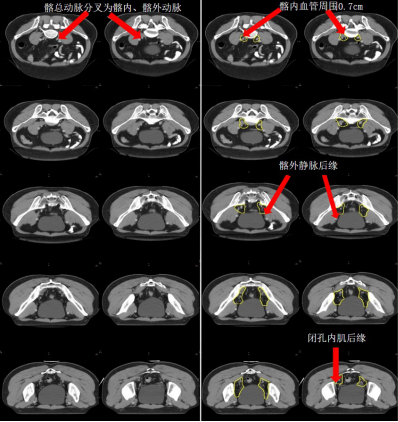

腹部骶前區-PS S (青色) (圖 5),邊界:

上界:腹主動脈分叉為左、右髂總動脈處或該區域內轉移淋巴結上方至少 0.5 cm;

下界:骶岬;

前界:腰椎前方 1 cm,髂總血管前 1.0 cm;

后界:腰椎前緣;

外界:髂總血管外側外 0.7~1.0 cm。

盆腔骶前區-PS (淡藍色) (圖 6),邊界:

上界:髂總動脈分叉為髂內、外動脈處/骶岬;

下界:肛提肌插入外括約肌處/直腸周圍系膜脂肪組織消失處,相當于尾骨尖水平;

前界:腰椎前方 1.0 cm/骶骨尾骨前方 1 cm/直腸系膜筋膜后緣;

后界:腰椎前緣/骶骨尾骨前緣;

外界:骶髂關節/髂肌內緣。

圖 5 直腸癌腹部骶前區 CTV 勾畫示例

圖 6 直腸癌盆腔骶前區 CTV 勾畫示例